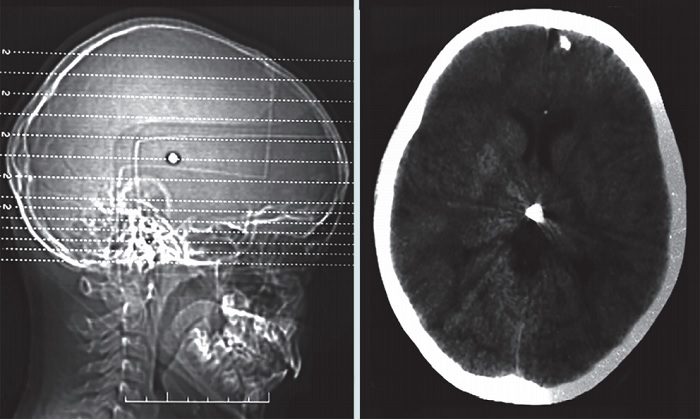

Las radiografías de cráneo (Figura 1) evidenciaron un cuerpo extraño radiopaco alojado en la parte central del interior del cráneo. La tomografía simple de cráneo (Figura 2) reportó un trayecto de entrada en línea paramediana izquierda, además de ruptura del ventrículo lateral izquierdo y alojamiento del cuerpo extraño en el tercer ventrículo. El servicio de Neurología y Neurocirugía realizó las pruebas de habilidades motoras y sensoriales, incluyendo los pares craneales, audición, habla, agudeza visual, coordinación, equilibrio, estado mental, además de cambios en el estado de ánimo y conducta durante su hospitalización, que resultaron normales en todo momento.

d. La permanencia lineal en la dirección que tomó el obús respecto al punto anatómico de entrada y el sitio final de alojamiento, cruzando la línea media interhemisférica (Figura 3)